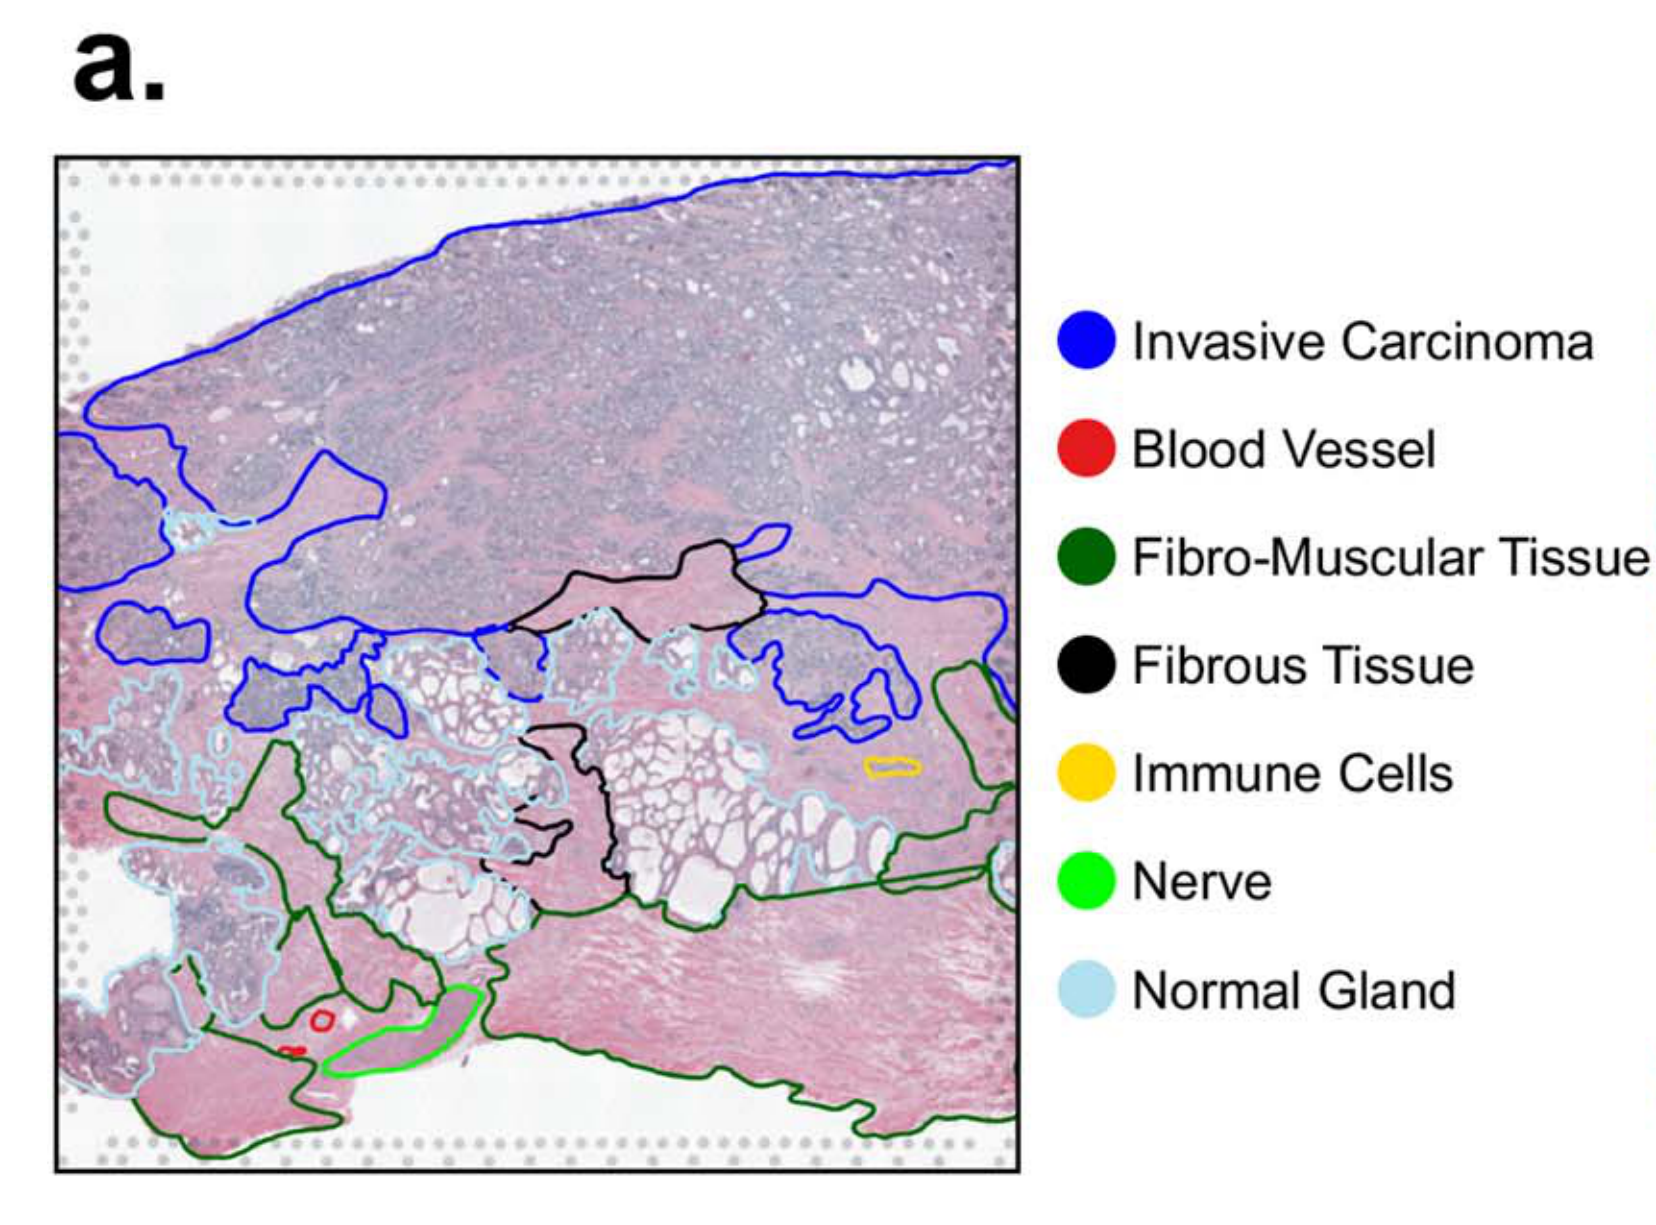

Jiang X. et al. - 2024

iIMPACT: integrating image and molecular profiles for spatial transcriptomics analysis

Condition Dimension

N/A

Data Components

Biological Annotation

Data

Metadata

None

Modality

Imaging-based

Resolution of observation

Multi-cellular

Visualized Elements

Observation

How are pathologist-defined tissue regions distributed across a cancer tissue section?

Biological

Tissue

Abstraction

Partial

Chart Type

Histological image

Communicative/Contextualization

Highlighting

Comparative Design

None

Layout

Spatial : Physical

Scalability Strategy

None (Item-level)